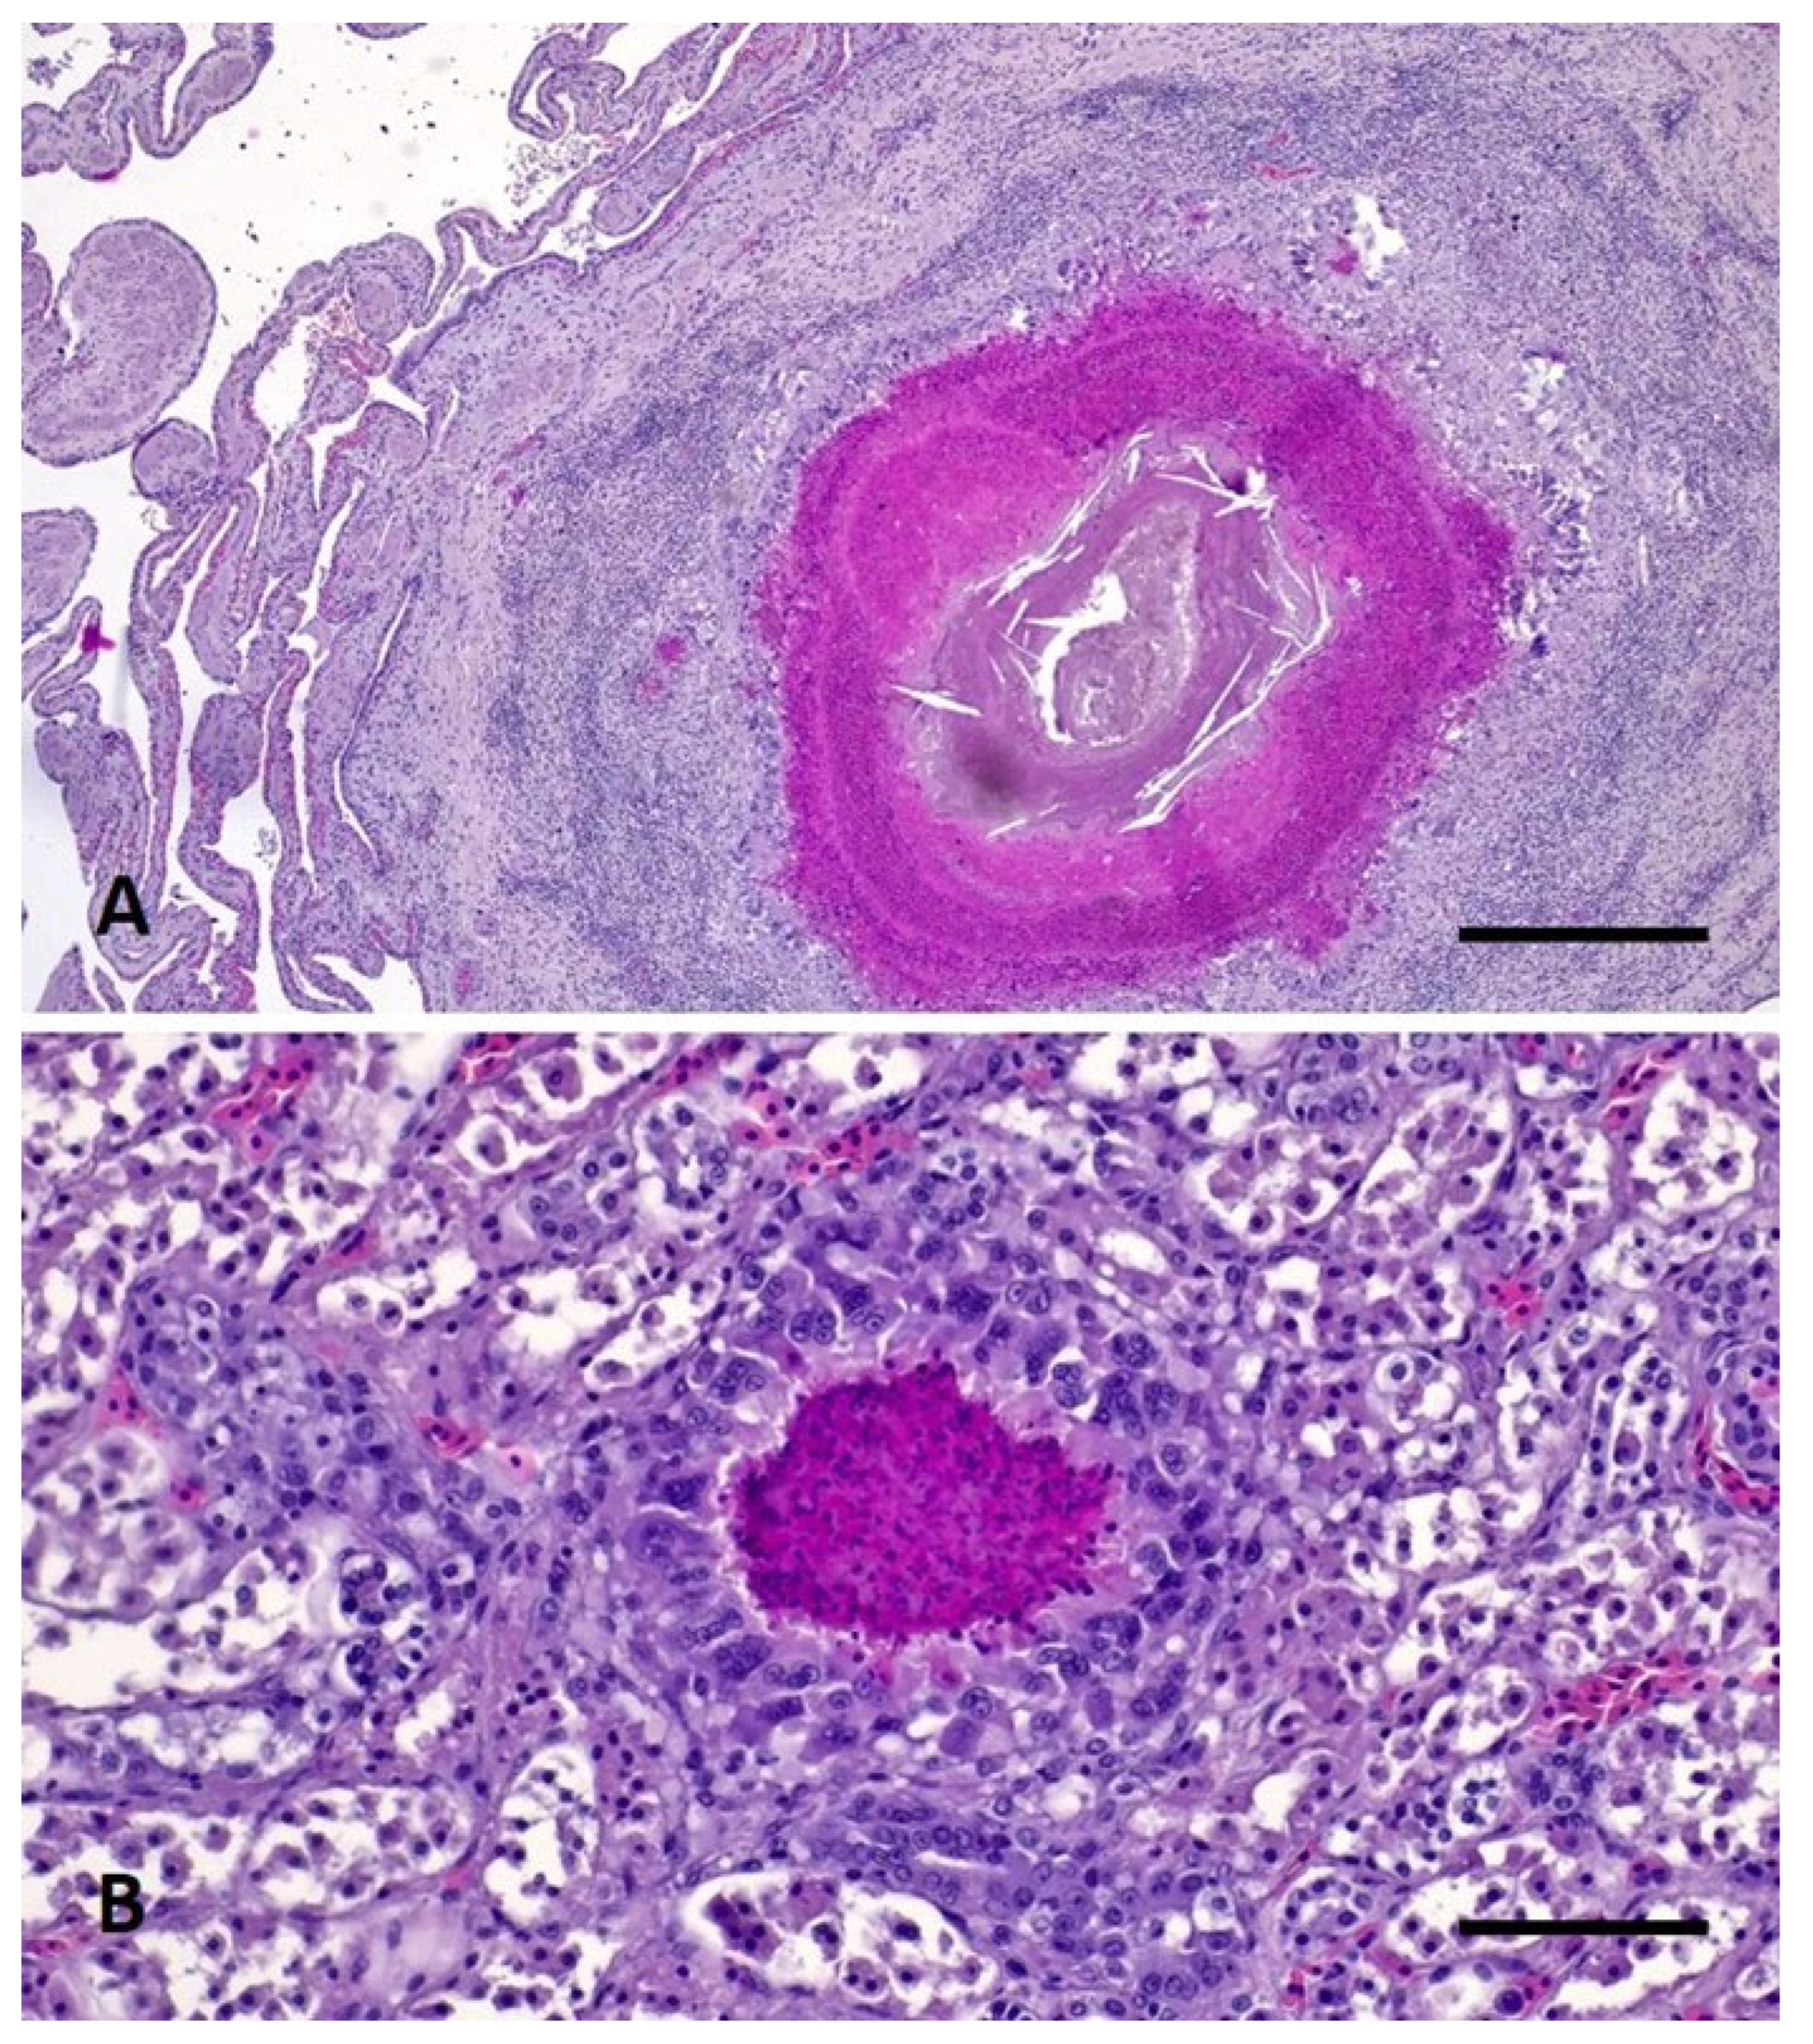

- Di Renzo, L.; De Angelis, M.E.; Torresi, M.; Di Lollo, V.; Di Teodoro, G.; Averaimo, D.; Defourny, S.V.P.; Di Giacinto, F.; Profico, C.; Olivieri, V.; et al. First Report of Septicaemic Listeriosis in a Loggerhead Sea Turtle (Caretta caretta) Stranded along the Adriatic Coast: Strain Detection and Sequencing. Animals 2022, 12, 2364. [Google Scholar] [CrossRef]